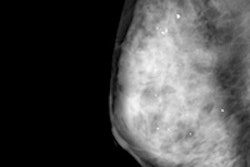

In this session, researchers will describe how screening digital breast tomosynthesis (DBT) offers sustainable and continually improving performance, such as increased cancer detection and fewer interval cancers.Led by Dr. Emily Conant from the University of Pennsylvania Health System, the group sought to examine whether improved screening performance from combining DBT with digital mammography was consistent over consecutive years. To do this, the researchers compared performance metrics from three years of DBT screening, which included more than 33,000 women. They tracked recall rates, cancer detection rates, positive predictive values, biopsy rates, and interval cancer rates.